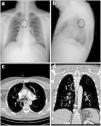

Case ReportA 45-year-old male applied to our department complaint with blood in sputum for 1 week. Physical examination was normal. There was no feature in his medical history other than 20 pack-years of smoking. Chest X-ray and computed tomography (CT) scans revealed the opacity in the posterior mediastinum, suggestive of a metallic foreign body (Fig. 1).

When the anamnesis was detailed due to these radiological findings, it was seen that he had a history of getting a piece of dishwashing scourer in his mouth while eating soup approximately 2 weeks ago. The patient's psychiatric history absence and the presence of eyewitnesses led to the realistic evaluation of this medical history. In the light of these data, surgery was planned with the preliminary diagnosis of a foreign body transesophageally migrated into the posterior mediastinum. Preoperative fiberoptic bronchoscopy was performed, revealing remnants of clots; however, no active hemorrhage was observed.